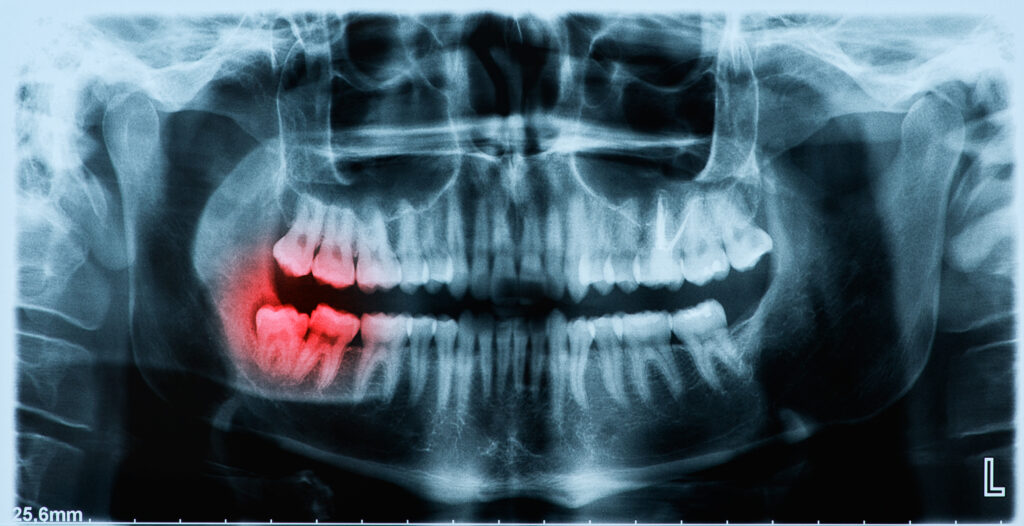

If your tooth is damaged or decayed, and is beyond repair your dentist may decide that the tooth should be extracted. Your dentist will talk you through your options beforehand, to ensure this is the only option for your case as teeth extractions are always a last option.

There are a number of different reasons that a tooth should be removed, for example, if you have the following:

Our clinicians will usually extract your teeth by themselves. However, sometimes the tooth extraction can be slightly more complicated than what they initially thought; therefore you may be referred to a Specialist Oral Surgeon either in a hospital setting or here at the practice.